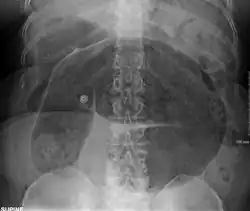

After taking a thorough history, the diagnosis of colonic volvulus is usually easily included in the differential diagnosis. Abdominal plain x-rays are commonly confirmatory for a volvulus, especially if a coffee bean sign is seen. These refer to the shape of the air-filled closed loop of the colon, which forms the volvulus. Should the diagnosis be in doubt, a barium enema may demonstrate a "bird's beak" at the point where the segment of proximal bowel and distal bowel rotate to form the volvulus.